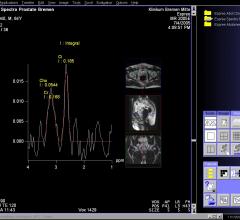

News and new technology innovations concerning how imaging technology can help diagnose and treat prostate cancer can be found on this channel.